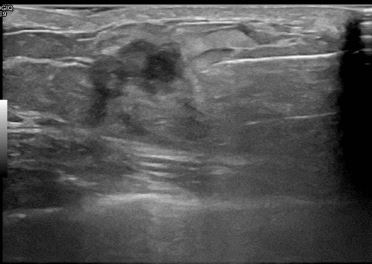

상기환자는 외부검사이상소견으로  내원하신 50대초반

여성분으로 의심스러운 좌측혹 조직검사 시행해 유방암 으로 진단되었습니다